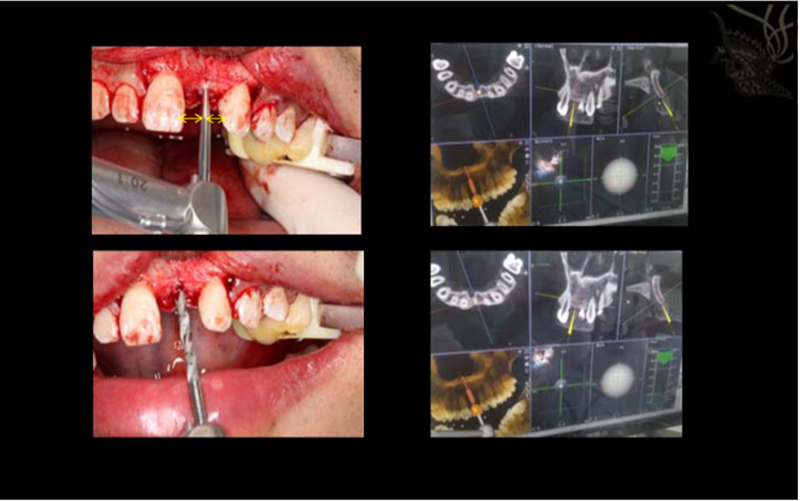

1.完成導航手術(shù)器械準備工作 2.軟組織翻瓣,充分暴露解剖形態(tài)

根據(jù)術(shù)前設(shè)計的種植方案開展手術(shù)

1.逐級備洞 2.術(shù)中,導航對種植區(qū)域位點,角度及深度實時引導 3.根據(jù)導航方案完成擴孔工作

植入種植體,根據(jù)術(shù)前方案,植體位點偏舌側(cè)

1.同期GBR植骨粉骨膜 2.進行縫合